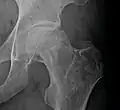

X-ray images of avascular necrosis in the early stages usually appear normal. In later stages it appears relatively more radio-opaque due to the nearby living bone becoming resorbed secondary to reactive hyperemia.[2] The necrotic bone itself does not show increased radiographic opacity, as dead bone cannot undergo bone resorption which is carried out by living osteoclasts.[2] Late radiographic signs also include a radiolucency area following the collapse of subchondral bone (crescent sign) and ringed regions of radiodensity resulting from saponification and calcification of marrow fat following medullary infarcts.

Radiography of avascular necrosis of left femoral head. Man of 45 years with AIDS.